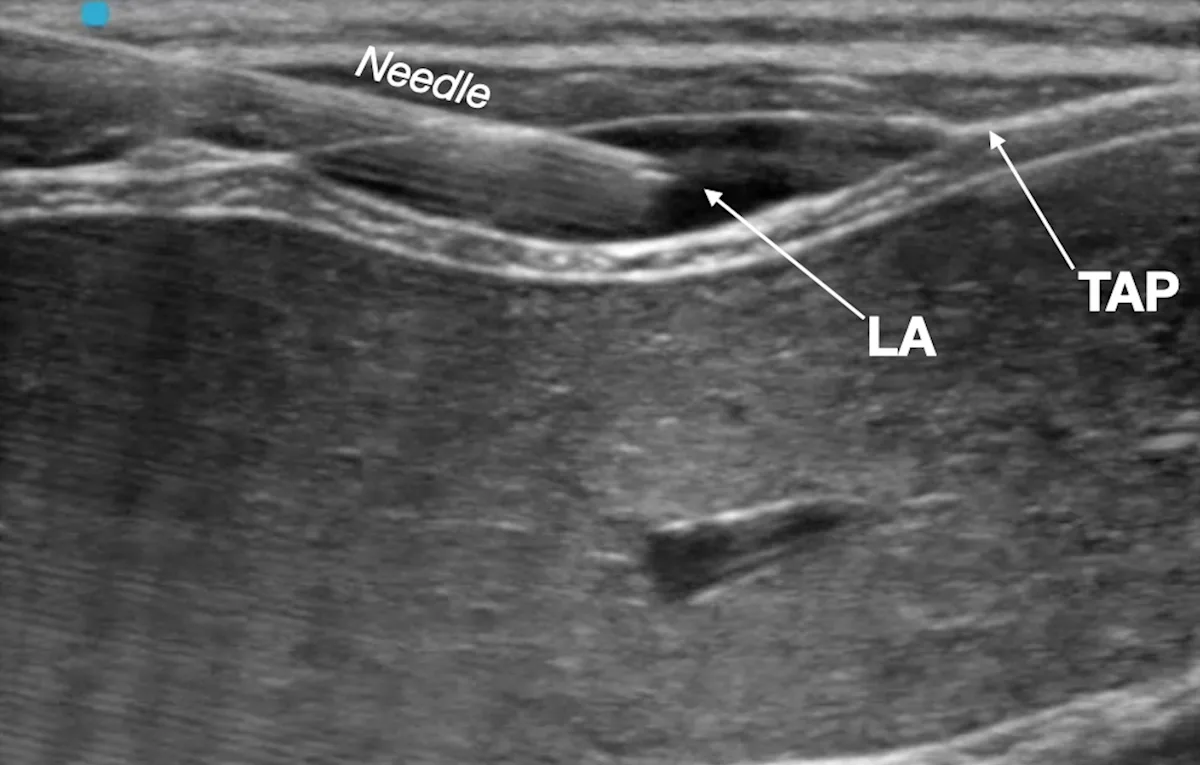

Step 10: Confirm Needle Placement

Rule out intravascular needle placement via negative aspiration test, and inject a small aliquot of the local anesthetic (LA) to confirm hydrodissection of the target fascial plane (ie, TAP).

Author Insight

Having an assistant handle the syringe and inject the local anesthetic is recommended.

The injected solution should separate the fascial plane, and anechoic fluid should be seen dissecting the fascia between the muscles. Gentle advancement of the needle into the target fascial plane during injection helps promote wider spread of the local anesthetic.